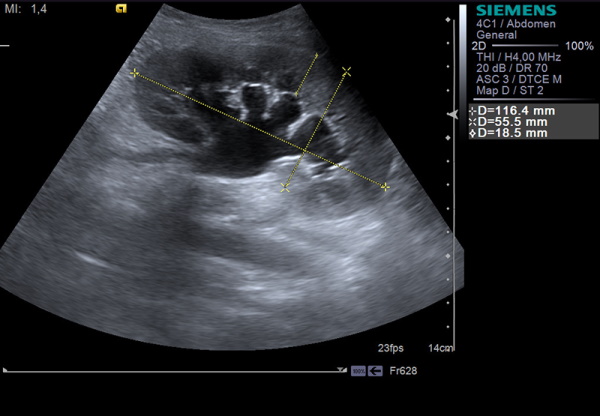

- УЗИ почек и малого таза, а также половых органов, кишечника, мочевого пузыря, брюшной полости, узлов лимфосистемы;